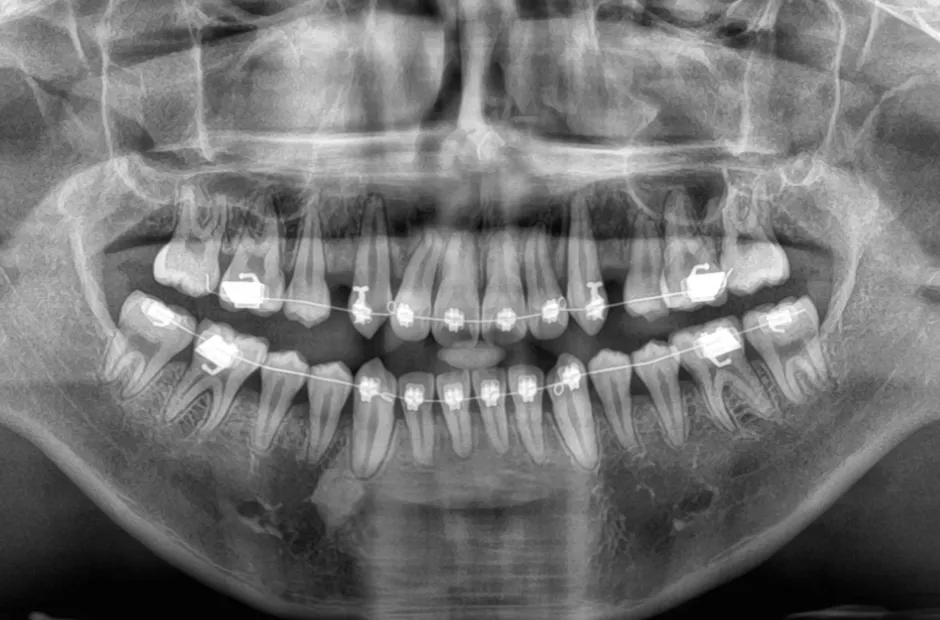

治療中